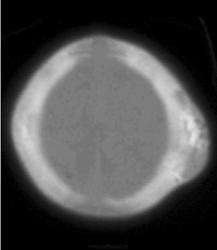

Острая кефалогематома.

Хроническая кефалогематома.